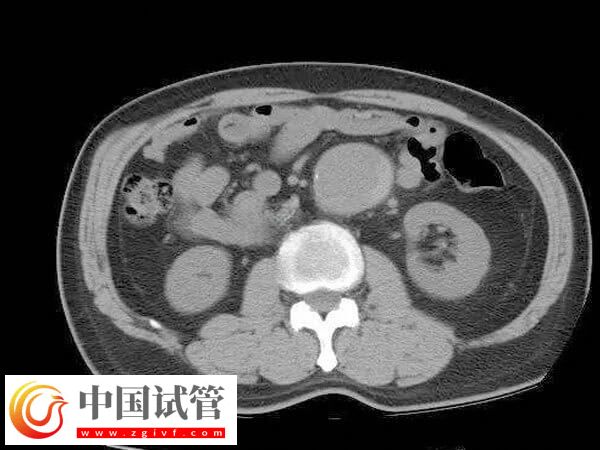

4、利用腹腔镜探查盆腔以了解子宫大小形态和位置与周围脏器关系。